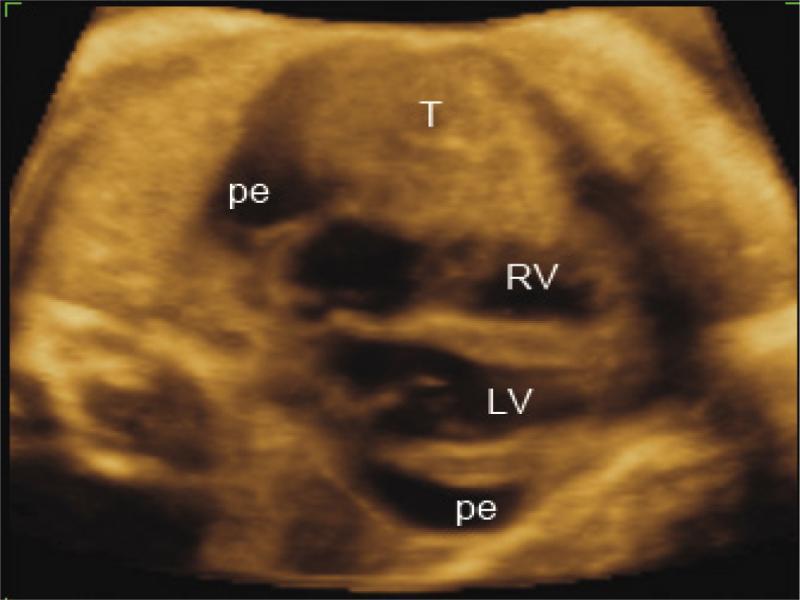

Original two-dimensional echocardiography picture which was taken during the first echocardiography exam. Pericardial effusion (pe) is seen. Large pericardial tumor (T) is located in front to the right ventricle (RV)